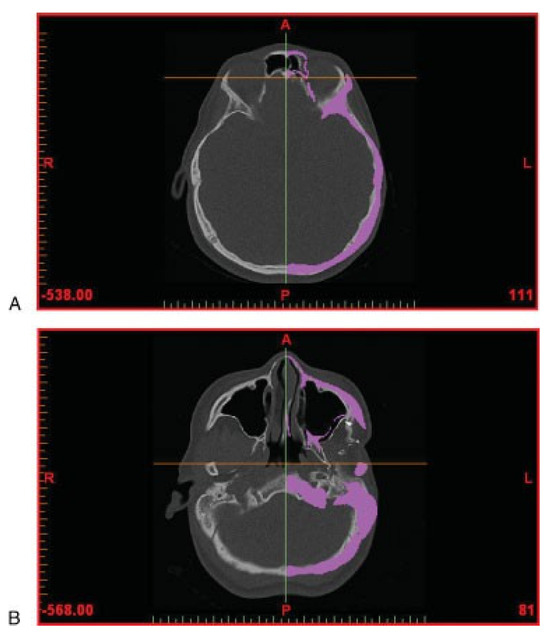

The aim of the surgery is to restore orbitozygomaticomalar symmetry; hence, the normal right orbitozygomaticomalar region was mirrored with respect to the midsagittal plane. In view of the facial torticollis and asymmetry, standardized bony landmarks were used to delineate the midsagittal plane [11]. The anatomic landmarks chosen were the foramen cecum, the posterior extremity of the sphenoid crest, and the middle point between both apophysis clinoid (Figure 2).

Figure 2. Computed tomography data (in axial view) showing anatomic landmarks for symmetry. (A) Foramen cecum. (B) Posterior extremity of the sphenoid crest.